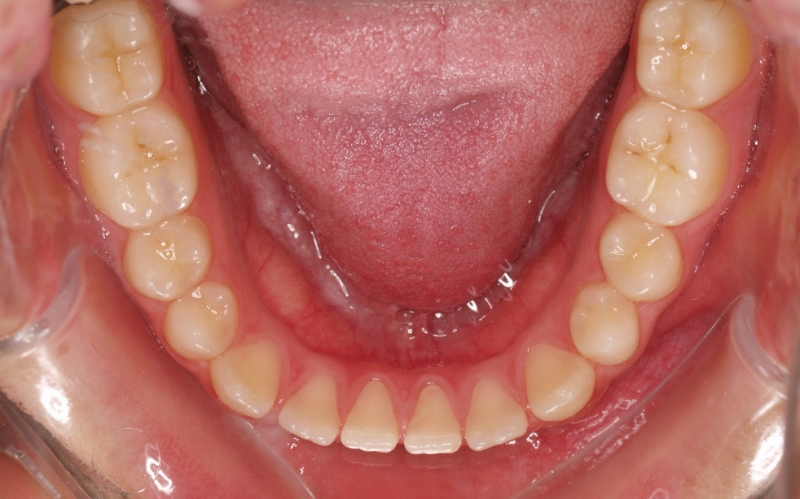

El stripping consiste en la reducción interproximal del esmalte entre los dientes posteriores y anteriores, así obtenemos espacio para alinear los dientes apiñados.

Chica de 17 años tratada en 1 año con stripping en los dientes inferiores